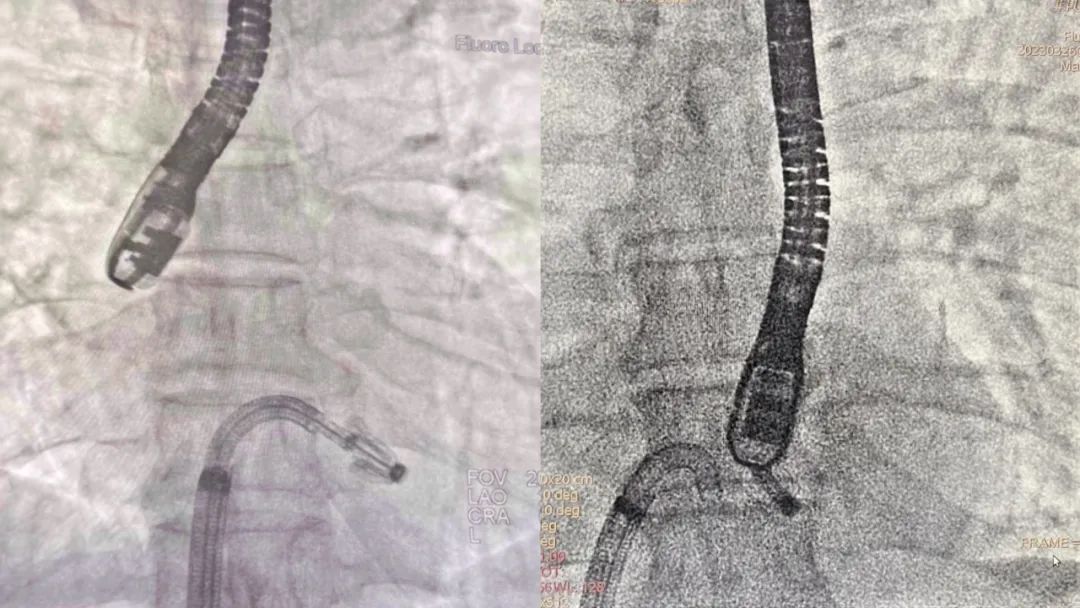

实施经导管二尖瓣缘对缘修复微创手术

据了解,经导管二尖瓣缘对缘修复微创手术是一项基于外科二尖瓣缘对缘修复手术的介入技术,采用二尖瓣夹合装置,经股静脉或心尖途径植入,在超声及X线引导下夹住二尖瓣反流区的前后叶并使之对合,从而达到减少或消除二尖瓣返流的效果。

食道超声指导下调整夹合器轴向后缓慢送入左心室

钳夹效果满意后释放夹合器

术中,刘宗军带领团队攻克了三大难点。难点一在于,二尖瓣3区紧邻房间隔,操作空间狭小,需要精确选取和定位房间隔穿刺点。难点二在于,3区瓣下腱索丰富,存在乳头肌、肌小梁等复杂结构,操作过程中可能造成腱索断裂等不良事件,会进一步加重瓣膜反流。难点三在于,手术中要持续精准进行超声引导。由于患者二尖瓣病变位于3区靠近后内交界位置,需要超声医生细致微调探头角度以获得清晰优良图像,为术者提供引导。针对这些挑战,手术医生与超声医生密切配合,选择靠上靠后的穿刺点,为后续操作提供足够的空间;食道超声引导在瓣上精确调整轴向,避免瓣下调整可能引起的腱索缠绕,用1枚夹子即获得满意的效果。